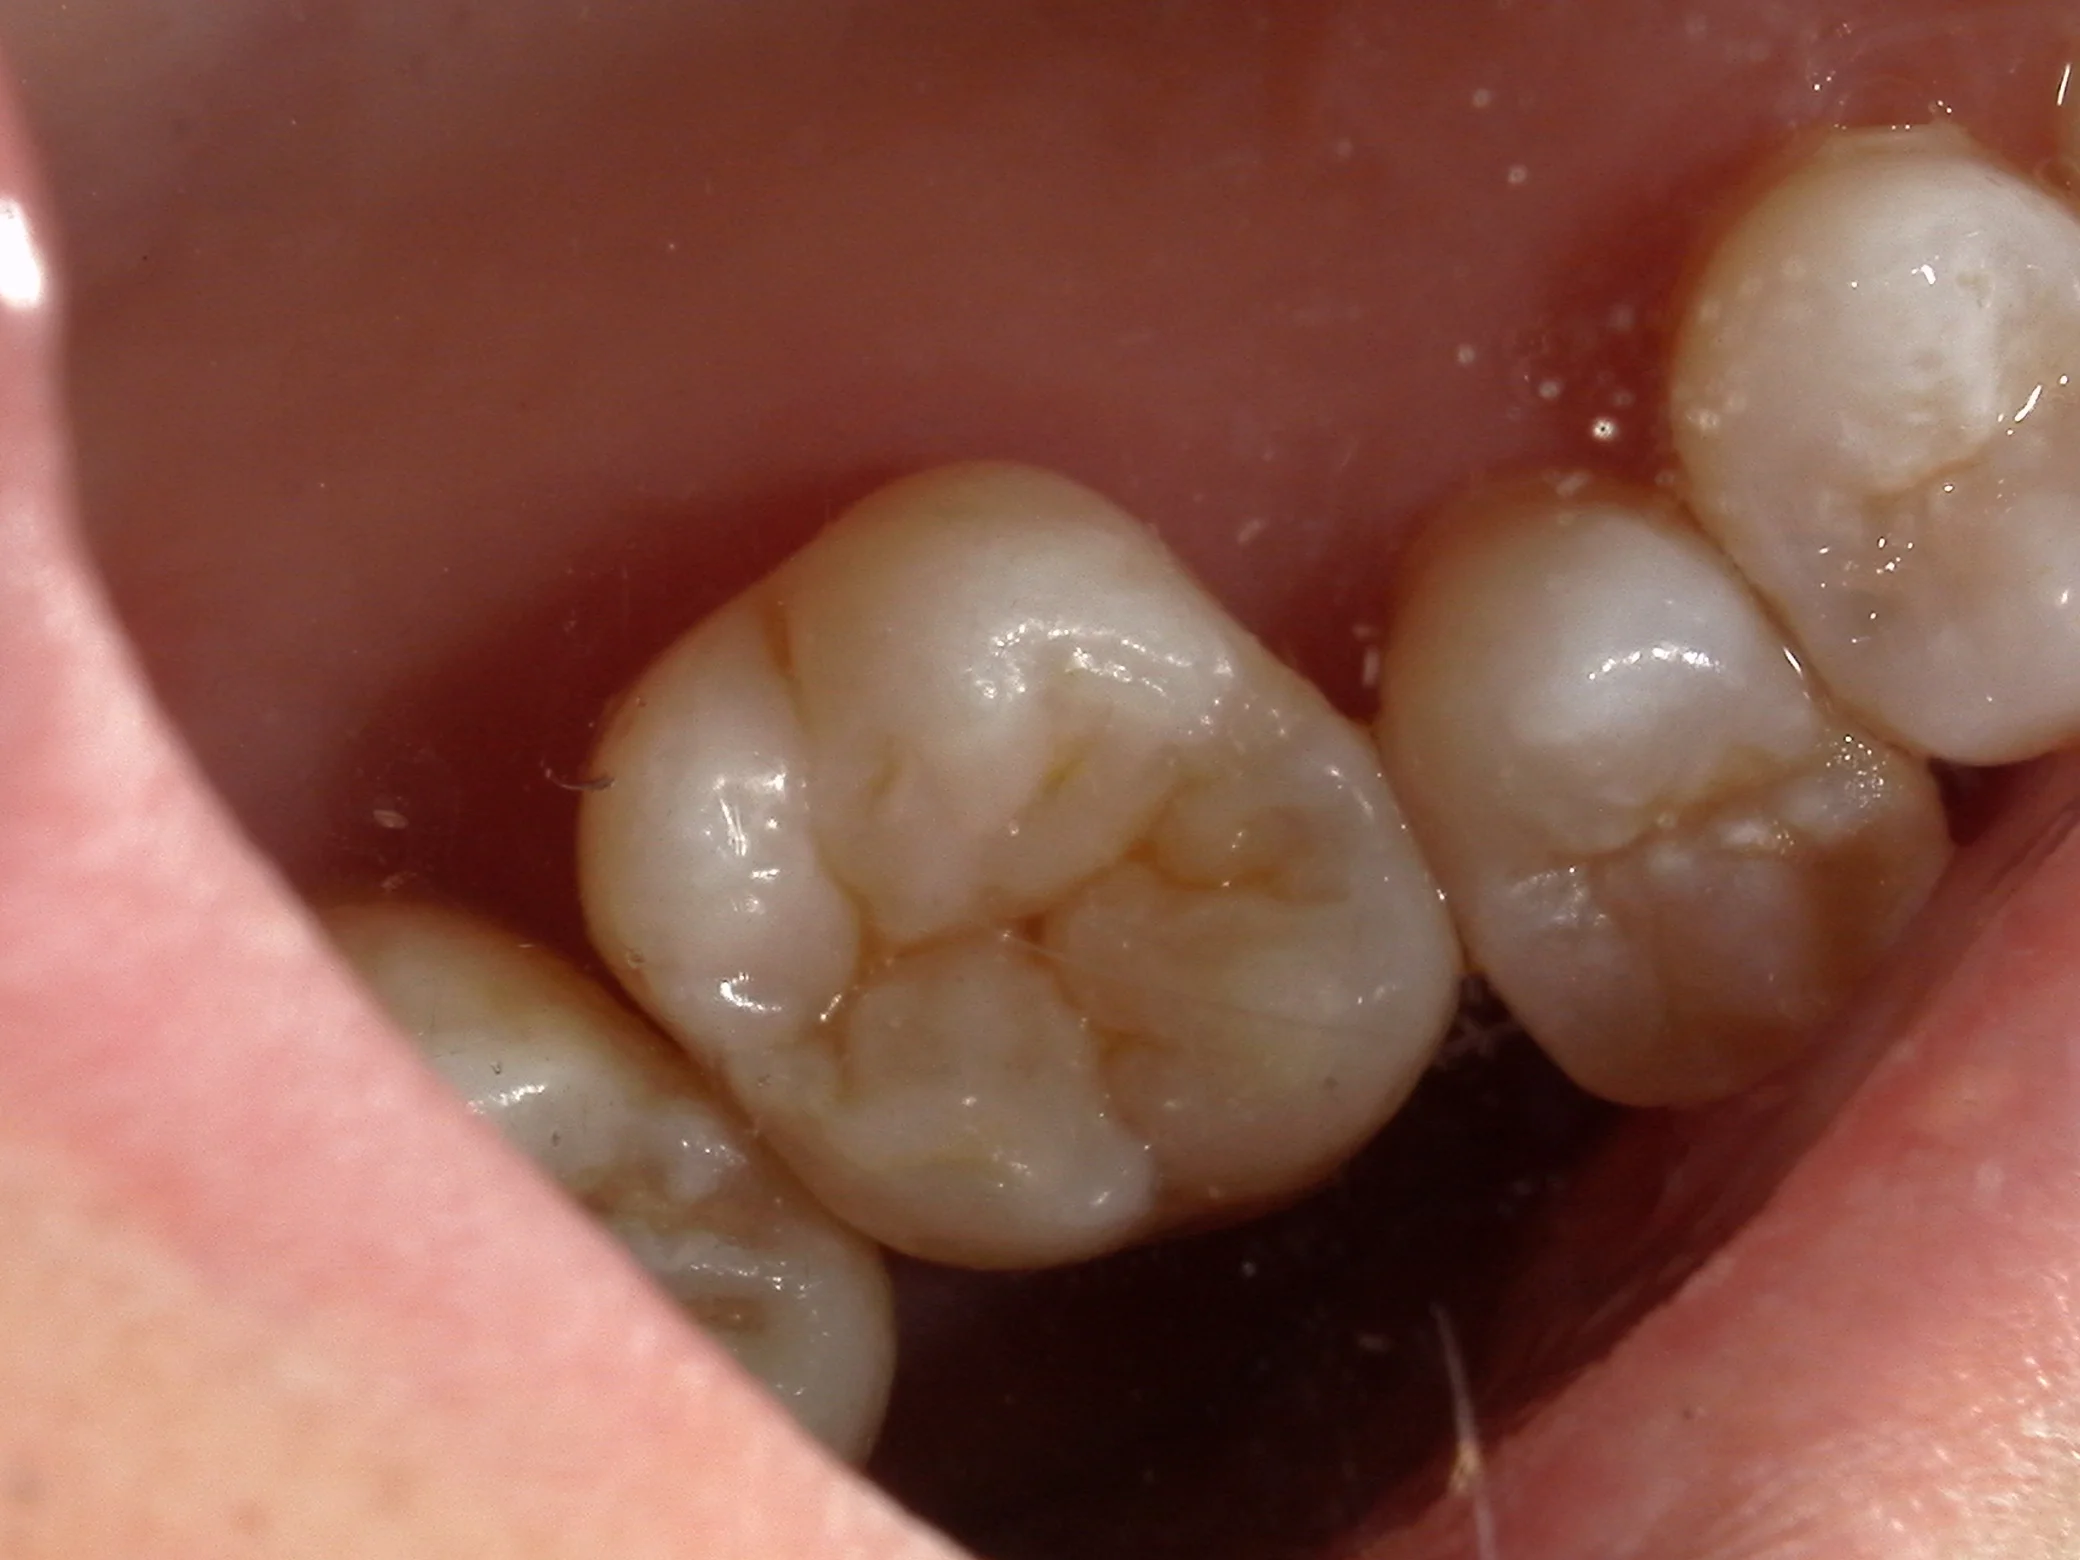

まず、普通の状態。

そして、色の違いを分かりやすくするためのシェード抽出画像。

どうでしょうか?

若干、中心裂溝(中央の黒い点)の深さを深くしすぎてしまった感じはありますが・・・

そこまで大きな色の違いは出ていないと思います。

そして術前術後の写真がこちらです。

咬合面のみなのでブラッシングもしやすいので、かなり長持ちしてくれるとは思います!